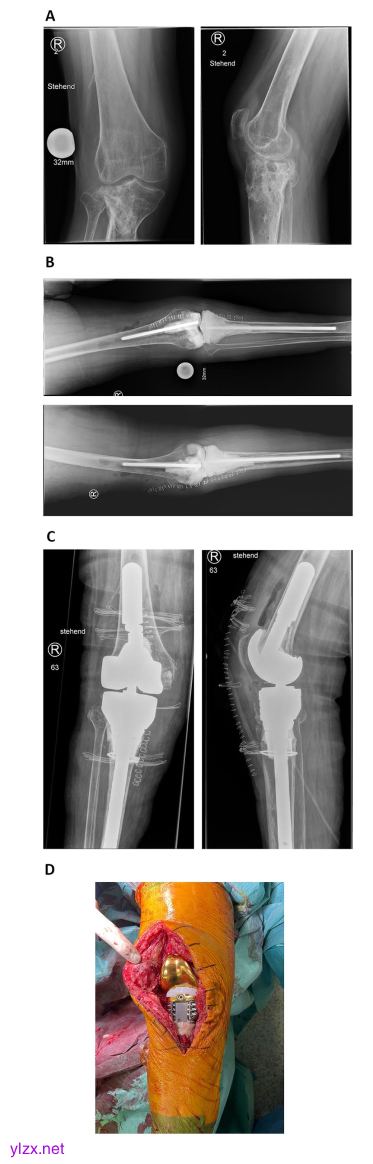

病例3显示,一名65岁的女性患者在2年前胫骨头骨折(AO 41C3)和切开复位内固定术后,出现感染性假关节和继发性膝关节骨性关节炎。在我们的门诊首次就诊之前,钢板接骨术已被移除。我们计划切除骨炎性骨,收集多个深层组织样本进行组织病理学和微生物学评估,并植入一个定制的关节垫片。A在我们的门诊首次就诊时展示术前X光片。临床上,患者经历了多向不稳定(KDC B)和腿轴的价值。箭头标示着骨炎骨。B第一次手术后的术后X光片显示,关节定制垫片严重侵蚀胫骨骨(KDC 4)和股骨髁骨水泥增强缺陷(KDC 2)